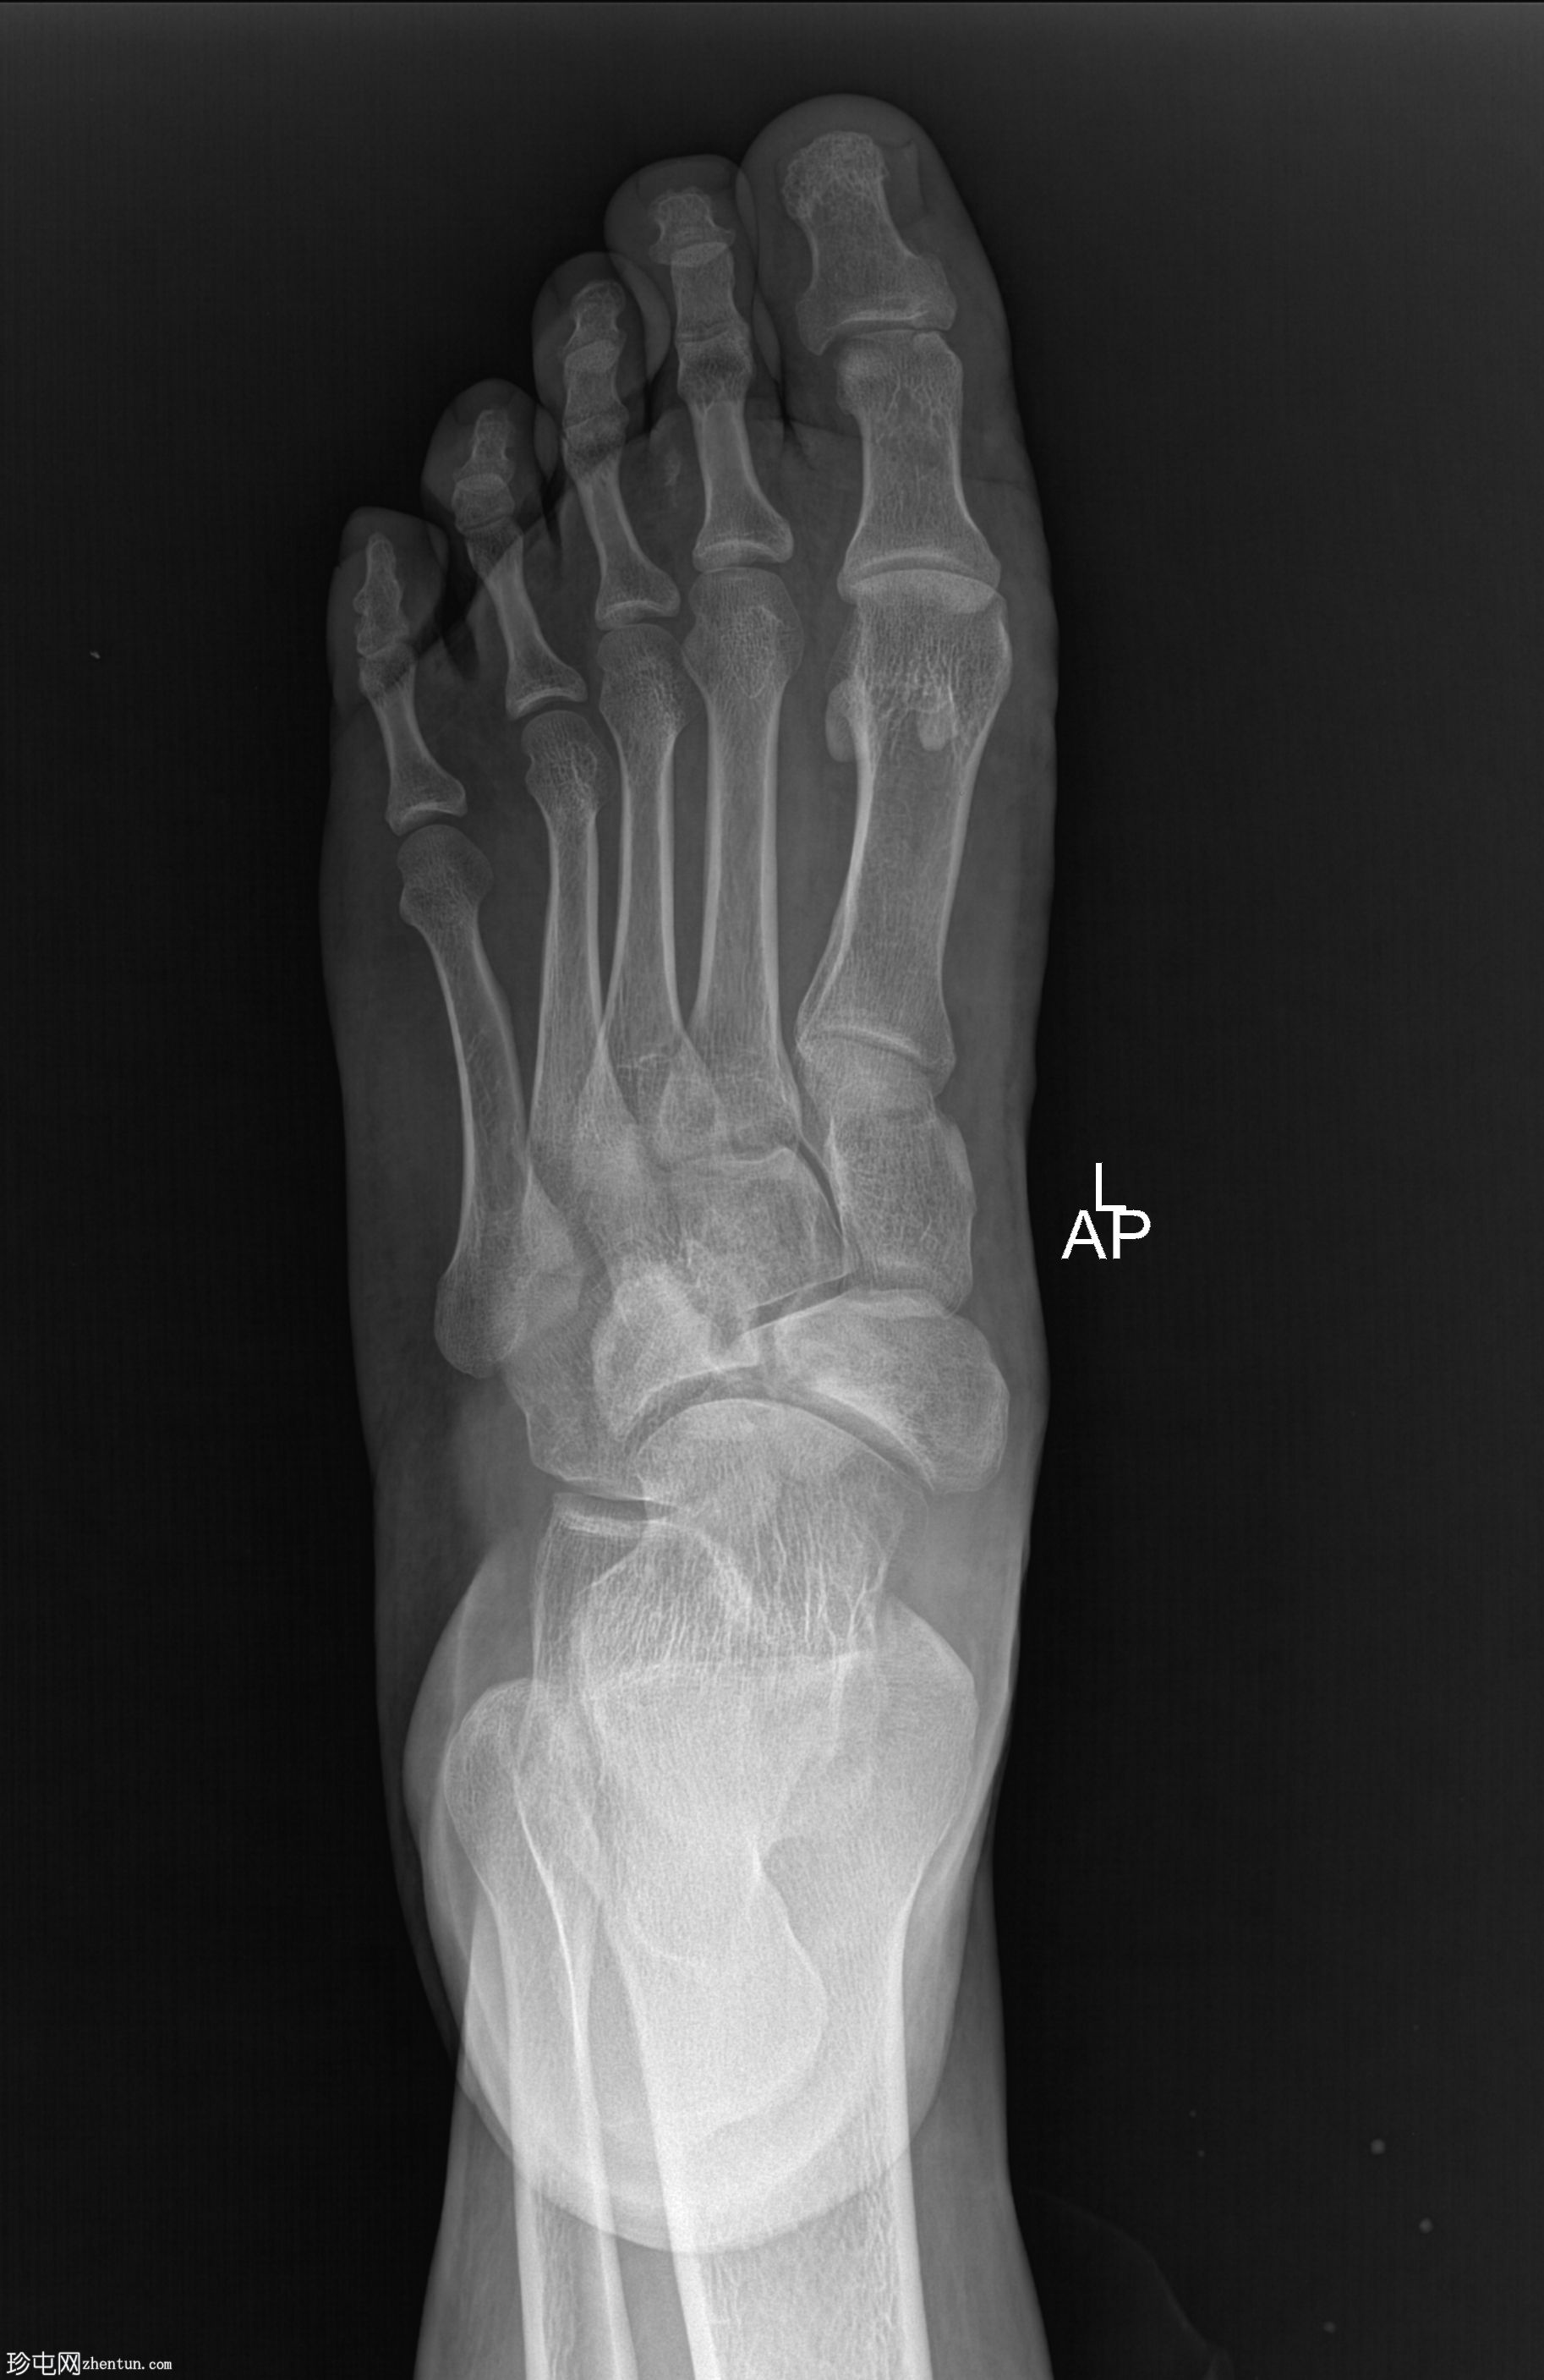

X光片

1.jpg

正面

舟骨呈二分状,由较大的内侧骨块和较小的外侧骨块组成。

内侧骨块呈逗号形。

外侧骨块及其外侧可见斑块状硬化,提示慢性应力相关病变或软骨结合处退行性反应。

邻近的跗骨和关节间隙似乎保存完好。